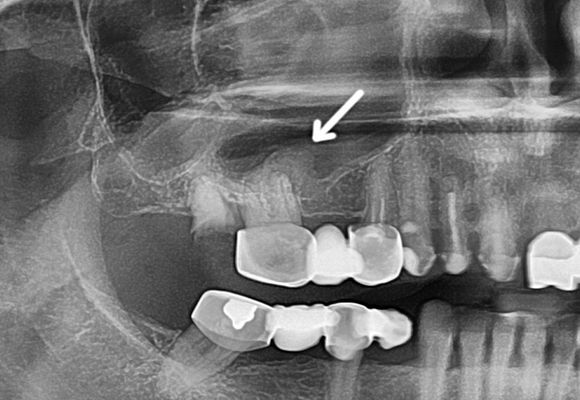

- Рентгенографії, лінійної, комп’ютерної чи магнітно-резонансної томографії, і ортопантомограммы (панорамного знімка) зубів;

- Рентгенографія (прицільна або панорамна) показує затемнення в ураженій камері і хворий зуб.

- Рентгенографія. Дає можливість знайти вогнище запалення і визначити його рівень.

- Рентгенографія. Широко використовуваний метод, що дозволяє виявити наявність в воздухоносной порожнини рідкого вмісту.

- Внутрішньоротовою рентген зубів. З його допомогою визначається стан кісткових структур в периапикальной (з’єднує зубні коріння з яснами) області, та наявність в ній сторонніх тел.

Діагностика даного захворювання проводиться на підставі скарг хворого, вивчення історії хвороби, зовнішнього огляду, риноскопії. Найбільш точний і поширений спосіб діагностики одонтогенного синуситу — рентгенографія носових пазух.